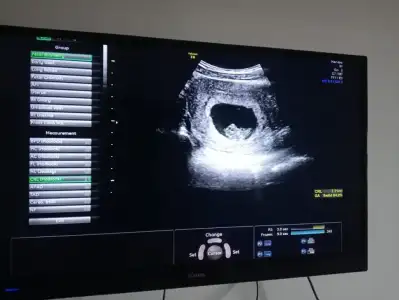

Kızlar 6+6 karından ultrason yorumlarmısınız 🌸🙏

Eklentiler

• IMG_20230419_115656.webp

IMG_20230419_115656.webp

17,8 KB · Görüntüleme: 92